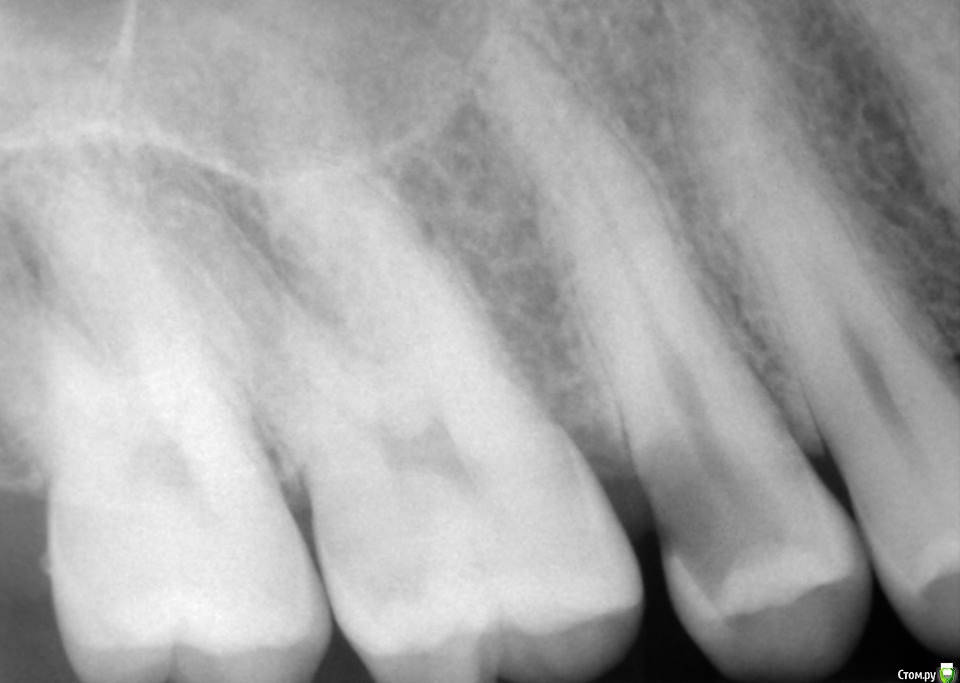

Kolchanov Опубликовано 23 июня, 2015 Поделиться Опубликовано 23 июня, 2015 Экструзия одиночного зуба для получения хоть какого-нибудь феррула. Подозреваю, что процедура не очень сложна и вполне модет быть освоена простым терапевтишкой, т.е. мной. Был бы очень благодарен, если бы кто-нибудь накидал своих мыслей по этому поводу, а еще лучше и фоток. И, конечно же, перечисление материалов. В одной из клиник, где я работаю, делают так иногда.После удаления штифтового зуба имеем поддесневой дефектhttp://s010.radikal.ru/i311/1506/49/4f3a03a5b53b.jpghttp://s010.radikal.ru/i313/1506/55/c752a532f478.jpgПациентка пожелала зуб сохранить. Теперь его тянут. И пятерочку еще в придачу.http://s014.radikal.ru/i327/1506/75/e9897bfb0e24.jpghttp://i024.radikal.ru/1506/99/1f1453b881ef.jpghttp://s017.radikal.ru/i434/1506/ea/caf4284659b4.jpghttp://s018.radikal.ru/i522/1506/ae/b2b54bddcdb8.jpghttp://s015.radikal.ru/i331/1506/7c/0efe752f8c35.jpgПока ничего сложного не вижу.У меня сейчас есть похожий случай. Но, послать в Москву... Не поедут. А на местного ортодонта как-то надежды мало. Я потом залью сюда фотки со своими мыслями. Может кто что присоветует...Спасибо! 1 Ссылка на комментарий

krokomot Опубликовано 23 июня, 2015 Поделиться Опубликовано 23 июня, 2015 Экструзия одиночного зуба для получения хоть какого-нибудь феррула. Подозреваю, что процедура не очень сложна и вполне модет быть освоена простым терапевтишкой, т.е. мной. Был бы очень благодарен, если бы кто-нибудь накидал своих мыслей по этому поводу, а еще лучше и фоток. И, конечно же, перечисление материалов. В одной из клиник, где я работаю, делают так иногда.После удаления штифтового зуба имеем поддесневой дефект Пациентка пожелала зуб сохранить. Теперь его тянут. И пятерочку еще в придачу. Пока ничего сложного не вижу.У меня сейчас есть похожий случай. Но, послать в Москву... Не поедут. А на местного ортодонта как-то надежды мало. Я потом залью сюда фотки со своими мыслями. Может кто что присоветует...Спасибо!Ох и любят у нас врачи заниматься вот таким лепиловом)))) Инженера в себе не скроешь)) Почему не с бреккетами? Приклеили несколько, дугу, цепочку проволку, что угодно, все же проще и предсказуемее (и быстрее) Ссылка на комментарий